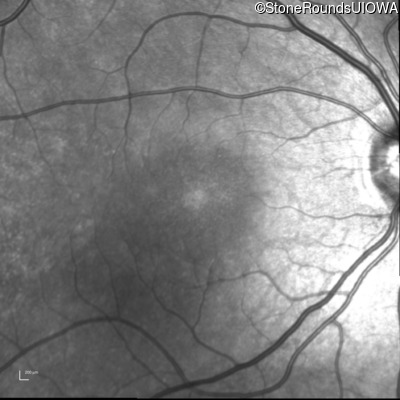

Infrared Fundus Photograph - Right - 20/32 -2 sc

Exemplar

Infrared Fundus Photograph - Left - 20/25 -2 sc